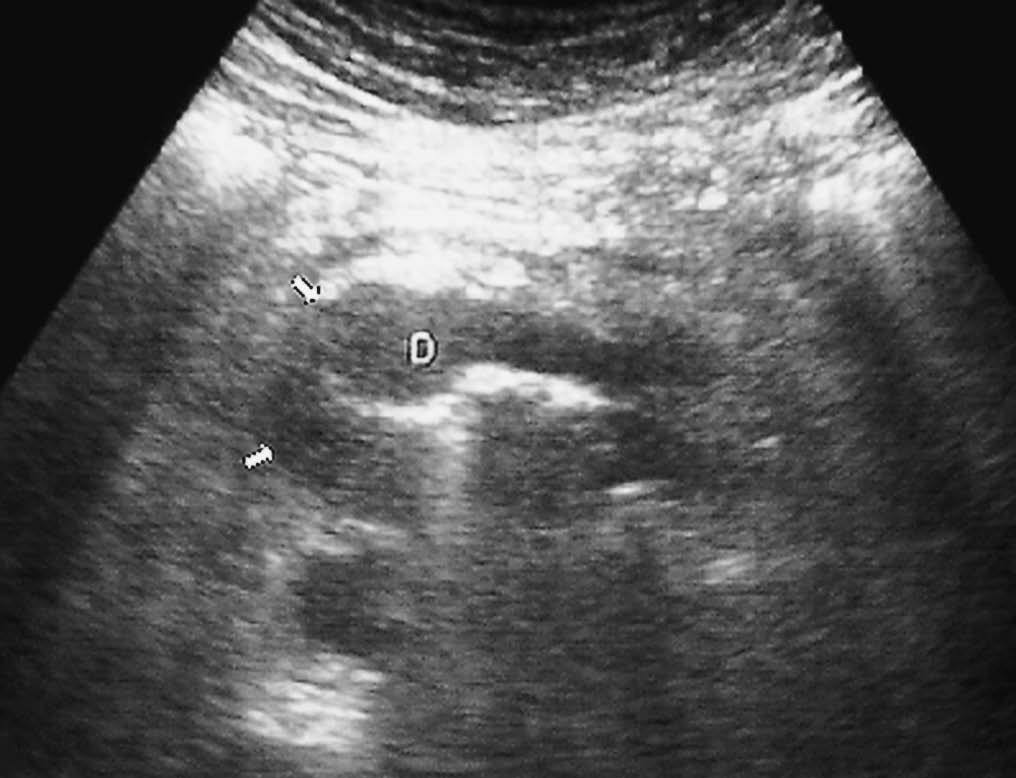

La forma más frecuente es la ausencia de rotación intestinal, que implica importantes alteraciones anatómicas valorables tanto en la ecografía como por la TC. Los principales hallazgos radiológicos son: alteración en la posición del duodeno, que no pasa entre la aorta y la arteria mesentérica superior (AMS); la localización en el hemiabdomen derecho de las asas de intestino delgado y en hemiabdomen izquierdo las de intestino grueso, y una verticalización o inversión de los vasos mesentéricos respecto a su posición normal, quedando la AMS a la derecha y la vena mesentérica superior (VMS) a la izquierda1,2 (fig. 1).

Fig. 1--Malrotación intestinal. (A) y (B) Tomografía computarizada con contraste oral e intevenoso mostrando inversión de la arteria mesentérica superior (AMS) (punta de flecha) y la vena mesentérica superior (flecha). La tercera porción duodenal (D) no cruza la línea media entre la aorta y la AMS, localizándose las asas de yeyuno a la derecha.